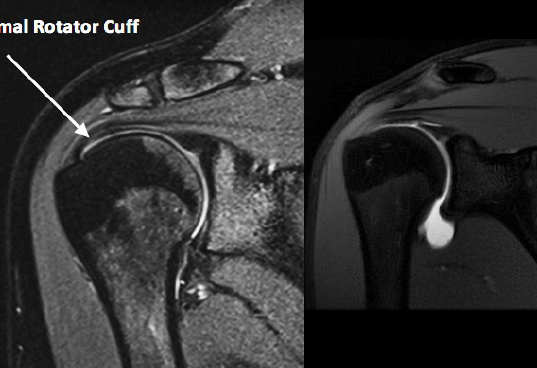

¿Cómo se ve el desgarro de manguito rotador en RM?

Hiperintensidad en T2

Mejor estudio de imagen para desgarro de manguito rotador

RM